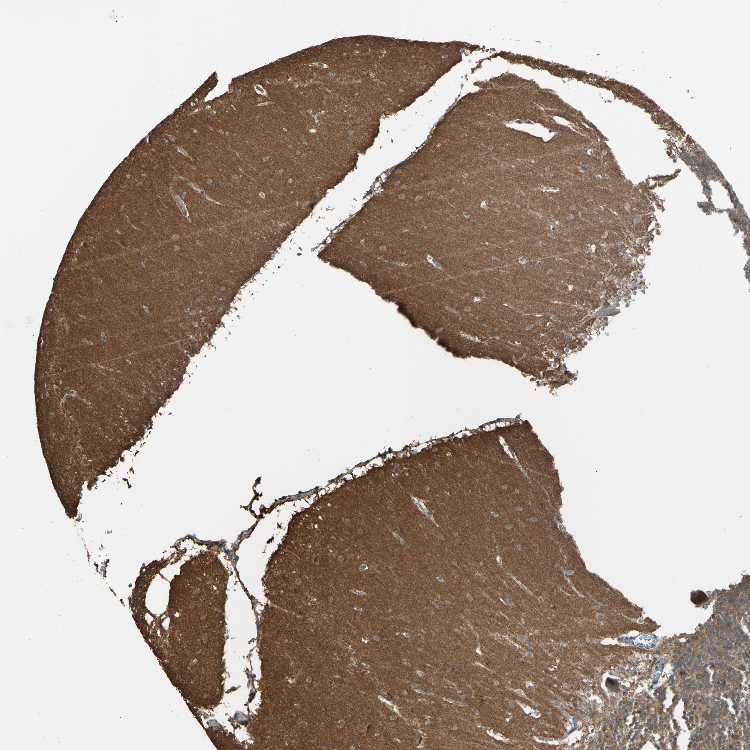

CEREBELLUM - Antibody stainingi

Antibody staining in the annotated cell types in the current human tissue is reported as not detected, low, medium, or high, based on conventional immunohistochemistry profiling in selected tissues. This score is based on the combination of the staining intensity and fraction of stained cells.

Each image is clickable and will lead to virtual microscopy that enables deeper exploration of all samples and also displays staining intensity scores, fraction scores and subcellular localization as well as patient and tissue information for each sample.

Antibody HPA007925Antibody CAB010286

Purkinje cells HighMedium

Cells in granular layer Not detectedNot detected

Cells in molecular layer HighNot detected